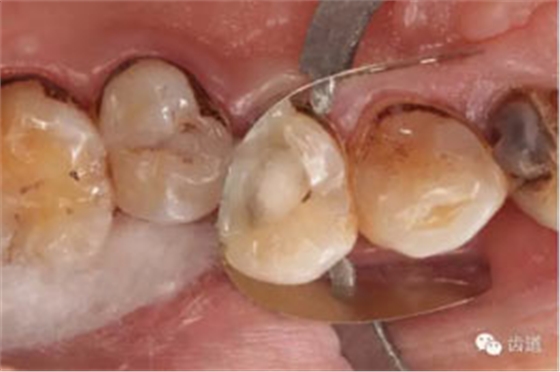

處理:去除暫封物,超聲根管蕩洗,清除氫氧化鈣糊劑,干燥根管,拍片顯示2506牙膠尖適合,根管內(nèi)放置AHplus,熱牙膠連續(xù)波根管充填。

數(shù)碼x攝影顯示:近中頰根及腭根根管充填恰填,遠(yuǎn)中根管有遺漏。

顯微鏡下反復(fù)探查根管,未探及遺漏根管口,放置棉球,zoe暫封。轉(zhuǎn)診上級(jí)醫(yī)生處理。